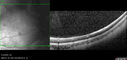

Bullous Retinoschisis - Asymptomatic54 viewsDec 17, 2025

Bullous Retinoschisis - Asymptomatic61 viewsDec 17, 2025

Bullous Retinoschisis - Asymptomatic57 viewsDec 17, 2025